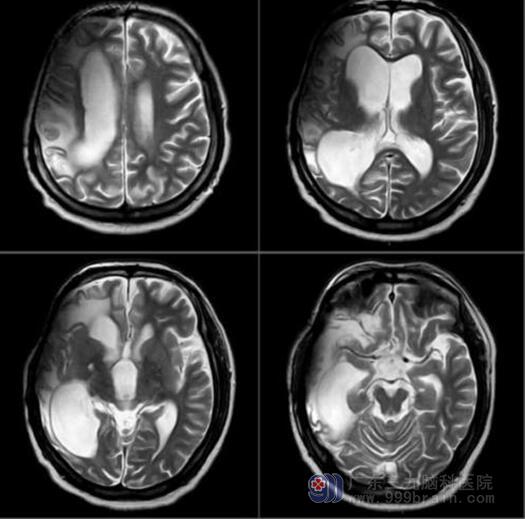

MR颅脑平扫结果提示:左侧额顶叶皮层异常信号,并颅内硬脑膜异常强化,考虑为感染性病变。